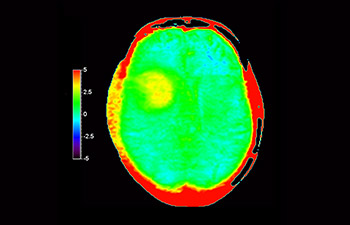

Glioblastoma recurrence

Brain imaging for glioblastoma recurrence

with 3D APT

3D APT (Amide Proton Transfer) is a unique, contrast-free, brain MR imaging method addressing the need for more confident diagnosis in neuro oncology. 3D APT uses the presence of endogenous cellular proteins, to produce an MR signal that directly correlates with cell proliferation, a marker of tumoral activity. 3D APT can support trained medical professionals in differentiating low grade from high grade gliomas and, in differentiating tumor progression from treatment effect1.